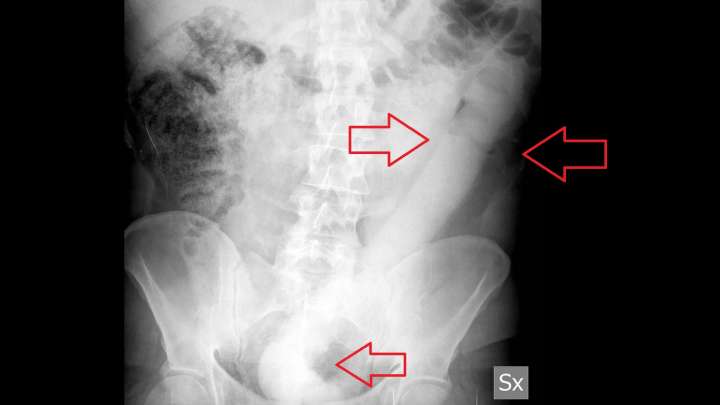

Italian Doctors Invent New Tool To Remove 23-inch Dildo From Man’s Rectum

Medical professionals are well-versed in removing large objects from people’s rectums. As the dozens of published case reports and thousands more back-offi